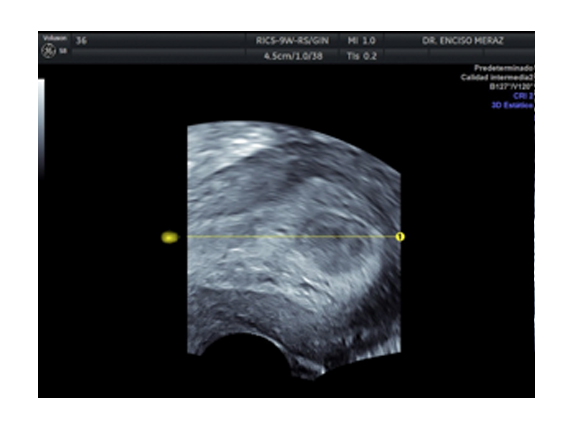

MIOMATOSIS

Leiomiomatosis, son los tumores benignos uterinos mas frecuentes de la mujer.

Se originan de las celulas musculares del utero. Tienen una frecuencia del 30% de todas las mujeres, estando con mayor frecuencia en la decada de los 30 y 40 años.